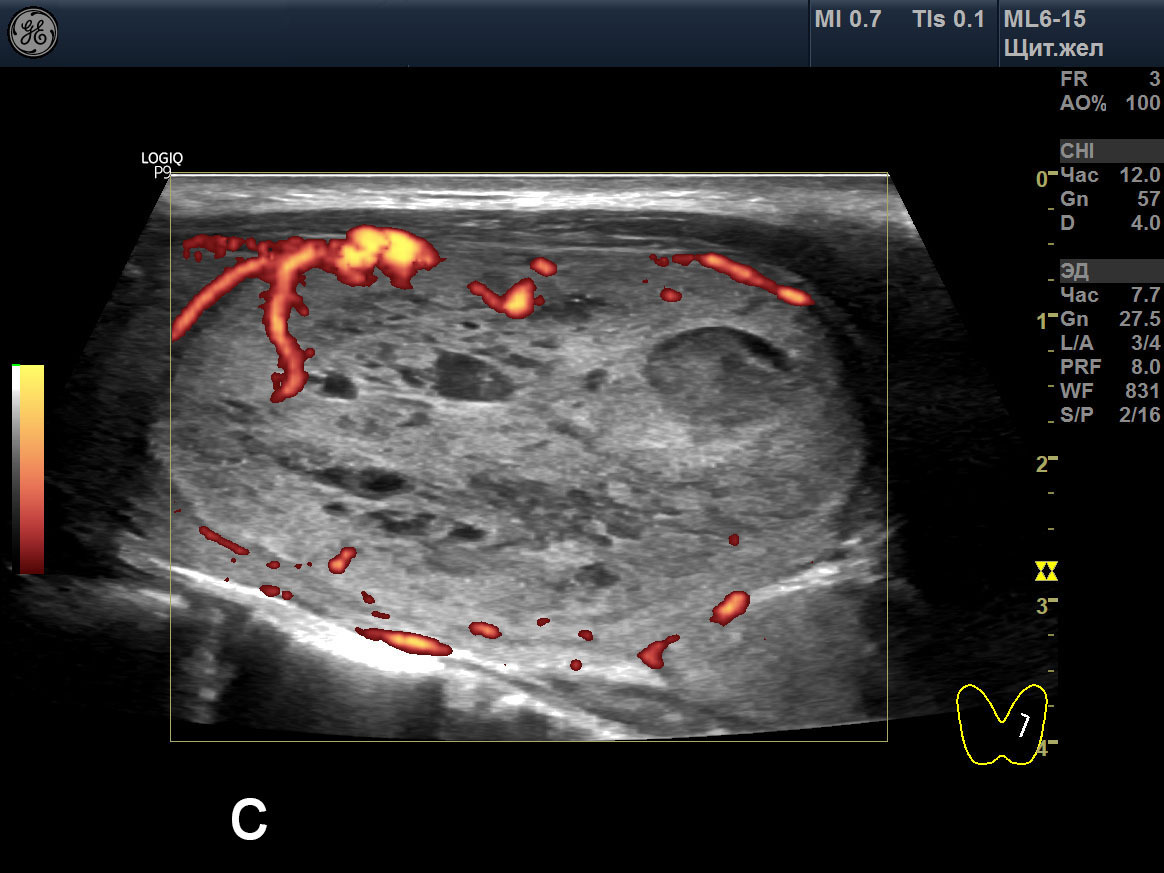

Теплый узел щитовидной

Теплый узел щитовидной 107 фотографий